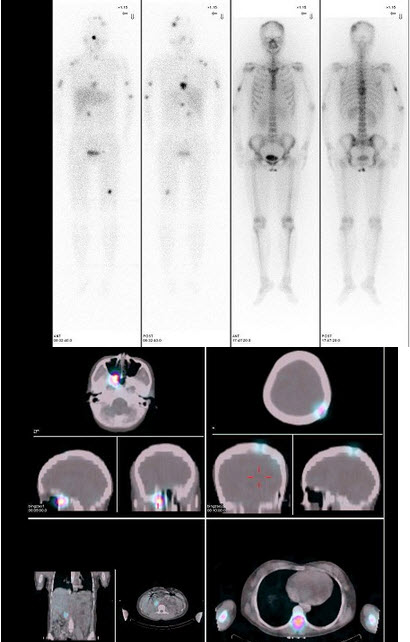

15、多项选择题

63岁男性,甲状腺滤泡状癌术后3年,行I全身显像及SPECT/CT图像融合如图,正确的诊断是()

A.未见明显转移灶

B.多发肺、脑转移

C.多发肺转移

D.无骨转移

E.有骨转移